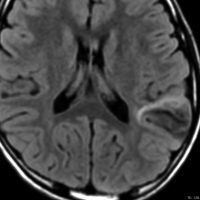

3歳で最初のてんかんらしいと言われる発作があり,その後は発作は見えず自動症と診断され徐々に学習能力の低下が認められ,7歳の時に外来を訪れました。週に3回くらい腹痛や嘔気があってすぐに眠くなってしまう。耳鳴がすごくてしばらく何も聞こえなくなってしまう,話も理解できなくなるなど,側頭葉てんかんの特徴をたくさんエピソードとして持っていましたが,症候性てんかんとは診断されませでした。側頭葉にどのような機能があるのかを証明してくれる症例でもあります。

典型的なDNTの画像で説明するまでもありません。ガドリニウムでは全く増強されませんでした。左上側頭回と角回の境界域に存在します。